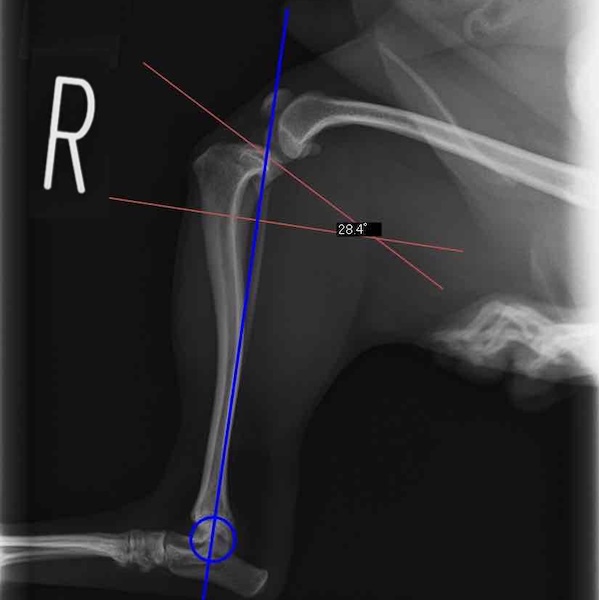

レントゲン検査 にて

右脛骨前方変位あり、ファットパッドサインあり

脛骨公平部角(TPA)の急峻を認める

手術前TPA 28.4° が術後TPA 11.7° に矯正されました。

術前TPA計測

手術前